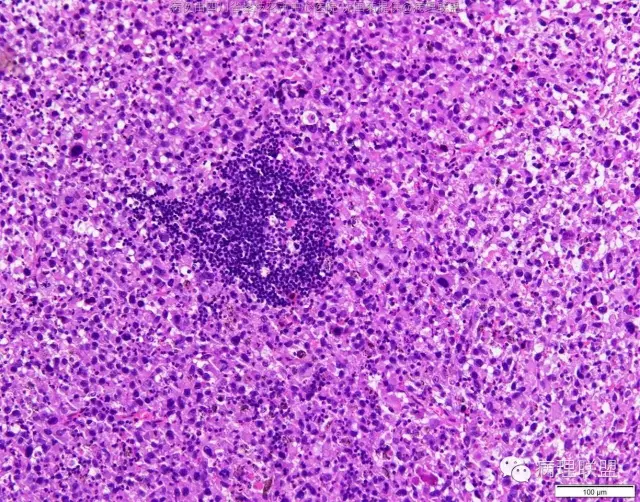

M/47 肺部占位( 肺大细胞癌?)

M/47 肺部占位,大小2*1*0.6cm(病例由四川攀枝花市中心医院 沈国菊提供,致谢!)

@沈国菊 肺大细胞癌的签发有时是个排他性诊断,我的体会:大细胞的标准:按淋巴细胞直径3倍来算,需要大于这个值,不能等于(从图给出,符合)。神经内分泌的标记(CD56 SYN CgA)完全阴性的可能性不是没有,建议重做试试;细胞的异型性大(符合);Ki67的指数高,应该非常高(您这里没有给出)。这仅仅是我个人体会,我说的不一定正确。

感谢您的精彩病例,采图非常漂亮,并且有标尺(特别赞)。魏老师,Ki-67阳性大于90%,送检7组淋巴结6/7见肿瘤转移。